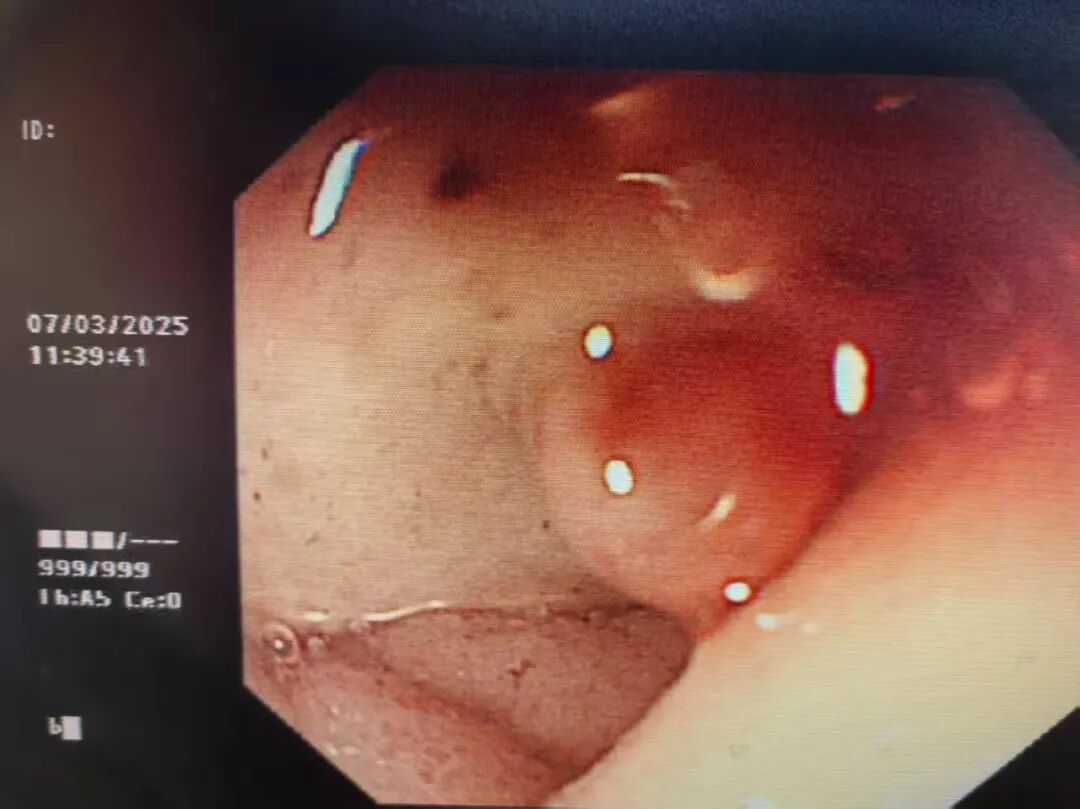

胃镜下病灶

患者入院诊断为急性上消化道出血(疑为吻合口溃疡并出血)、急性失血性贫血(重度)、慢性非萎缩性胃炎、胃穿孔术后以及幽门螺旋杆菌感染。后续完善相关检查,血常规-五分类:红细胞压积 0.089↓,血红蛋白 30(g/L)↓;血清蛋白三项测定:白蛋白25.3(g/L)↓;BNP3440.21(ng/L)。胃镜检查提示:1、十二指肠球部巨大溃疡并出血;2、胃粘膜贫血相;3、胃潴留。患者溃疡巨大且狭窄,无法窥全貌,内镜下止血风险极高(止血成功率低、再次穿孔可能性极大),在血源紧张的情况下,外科手术风险也极高,一旦再次出血,患者随时面临死亡。